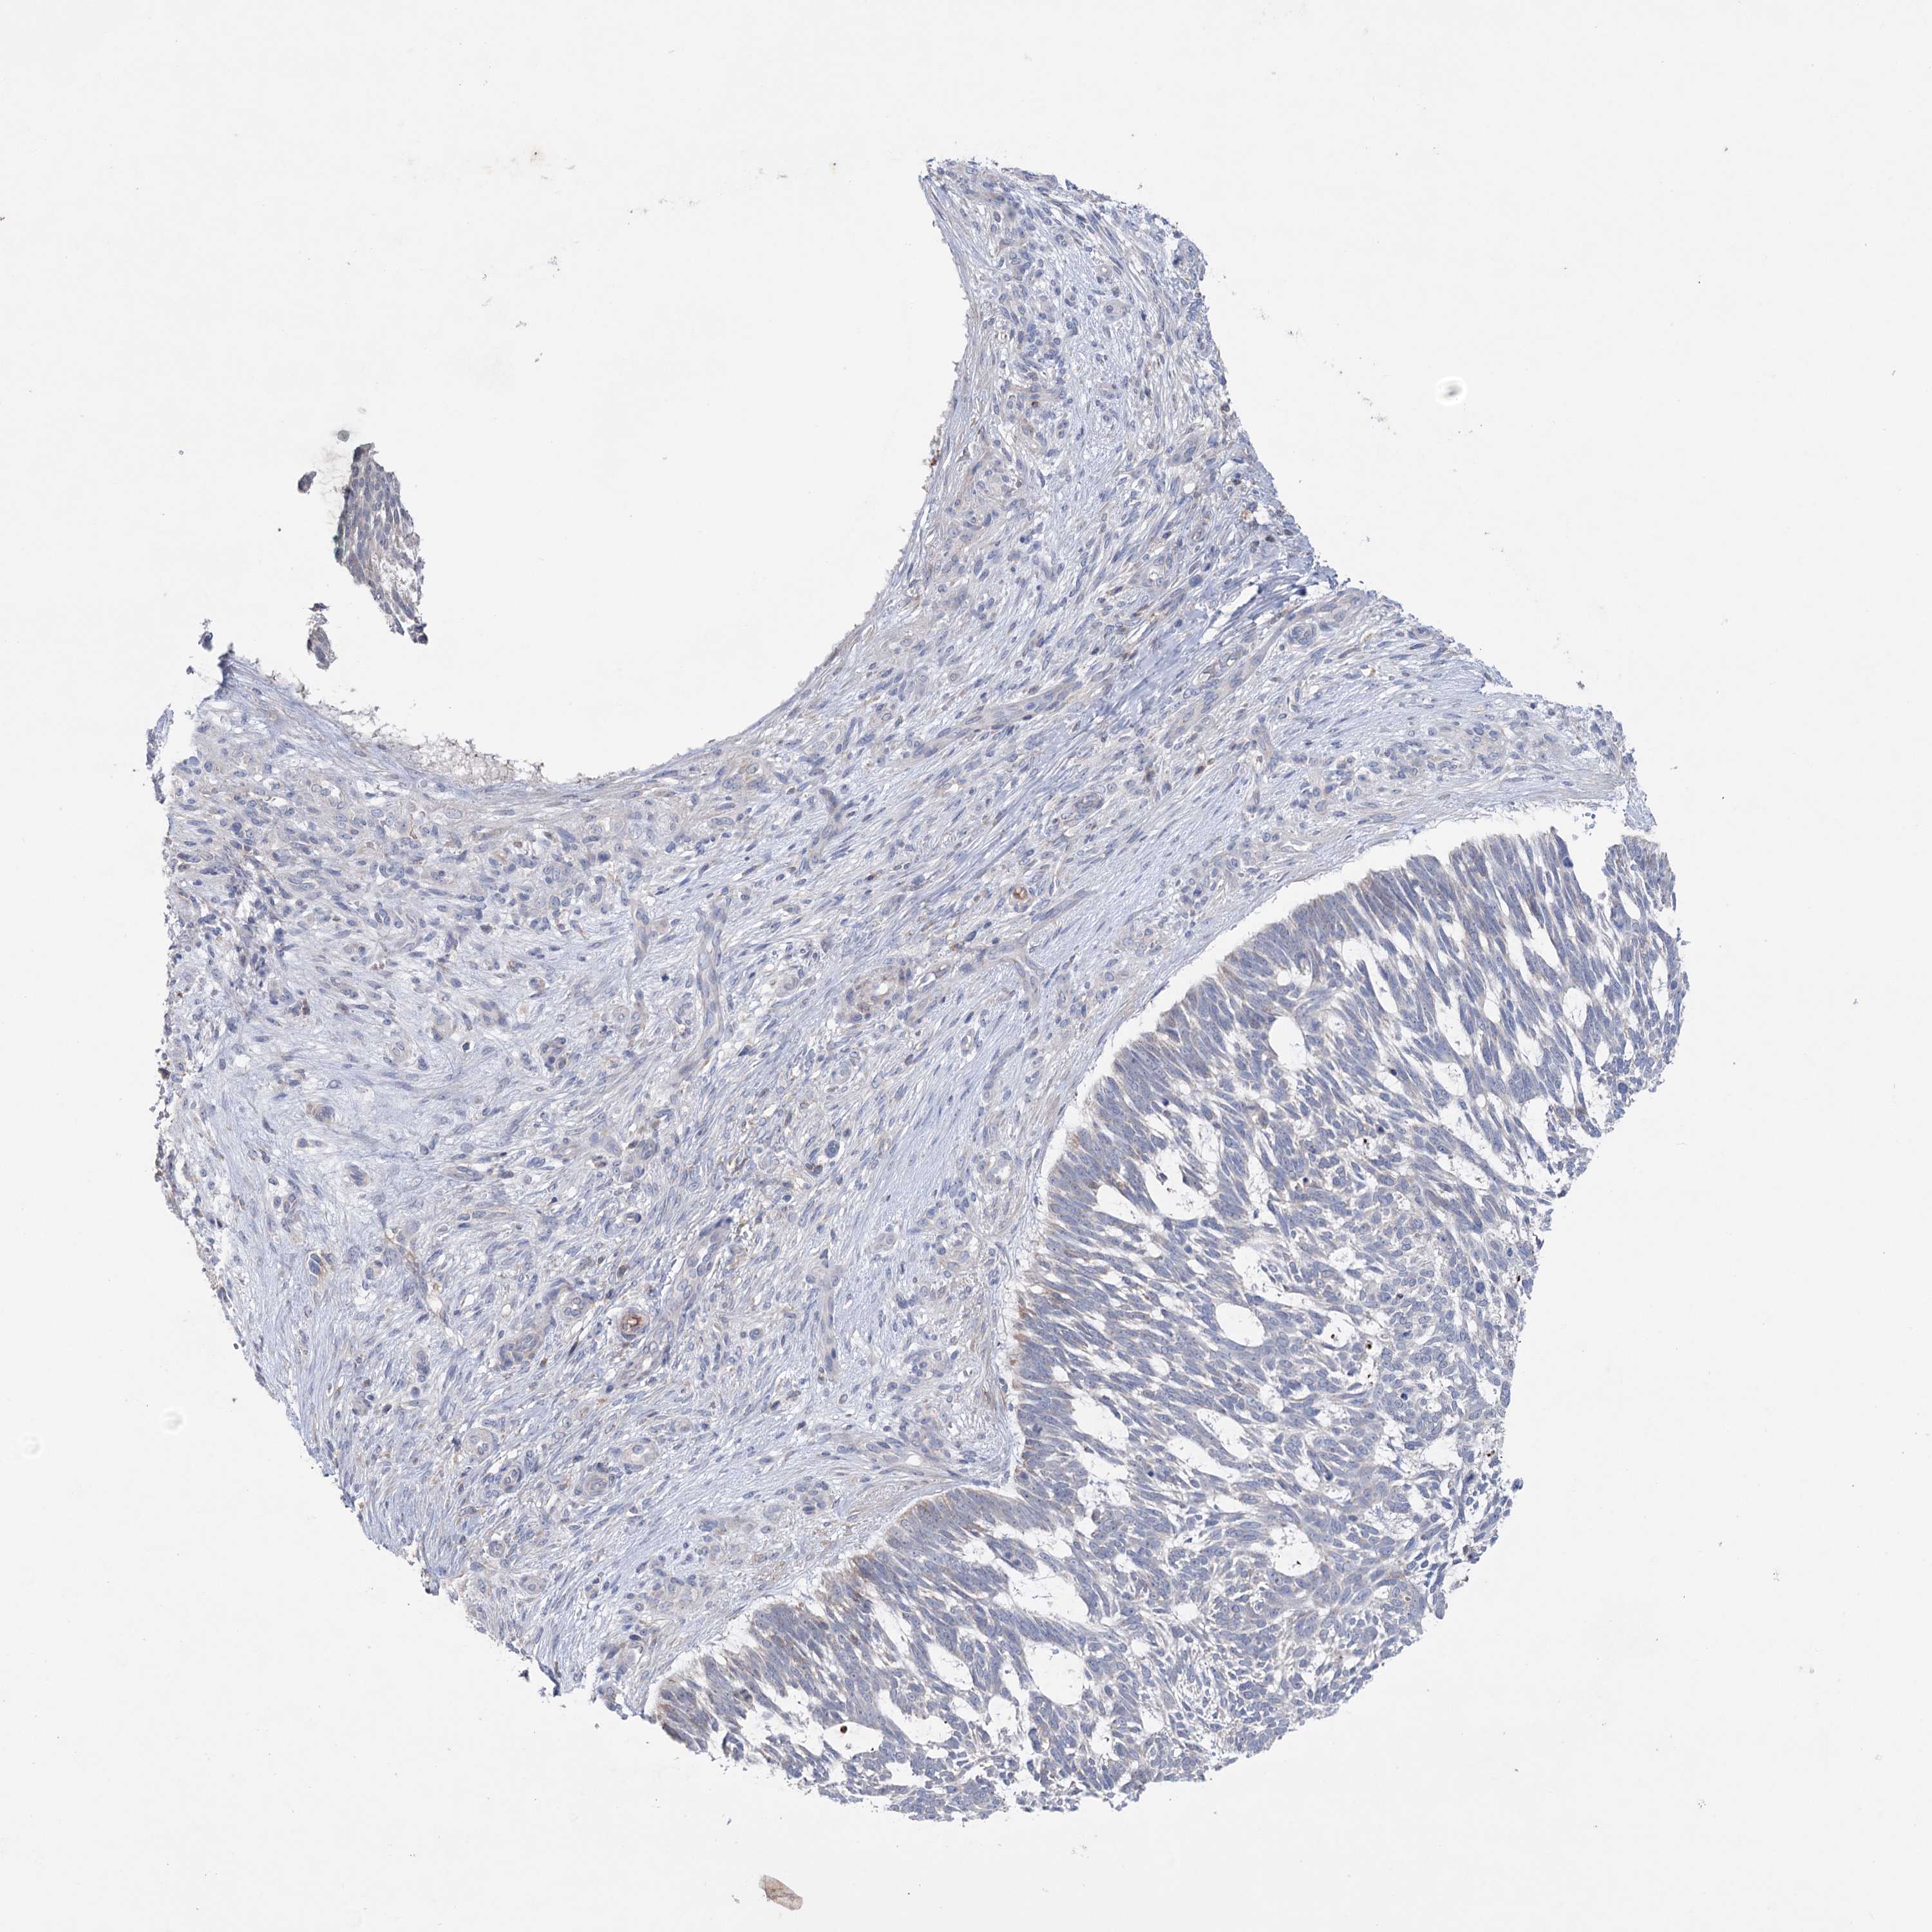

SKIN CANCER - Protein expressioni

A mouse-over function shows sample information and annotation data. Click on an image to view it in a full screen mode. Samples can be filtered based on level of antibody staining by selecting one or several of the following categories: high, medium, low and not detected. The assay and annotation is described here.

Antibody stainingi

Antibody staining in the annotated cell types in the current human tissue is reported as not detected, low, medium, or high, based on conventional immunohistochemistry profiling in selected tissues. This score is based on the combination of the staining intensity and fraction of stained cells.

Each image is clickable and will lead to virtual microscopy that enables deeper exploration of all samples and also displays staining intensity scores, fraction scores and subcellular localization as well as patient and tissue information for each sample.

Antibody HPA038390

Basal cell carcinoma

Squamous cell carcinoma, NOS

Squamous cell carcinoma, metastatic, NOS